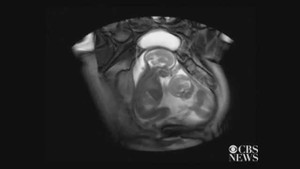

(VTC News) - Cặp vợ chồng cho biết họ đã rất sốc khi siêu âm cho thấy cặp song sinh họ đang mong đợi có tới hai gương mặt hoàn toàn đối xứng và hai bộ não kết nối với một thân não.